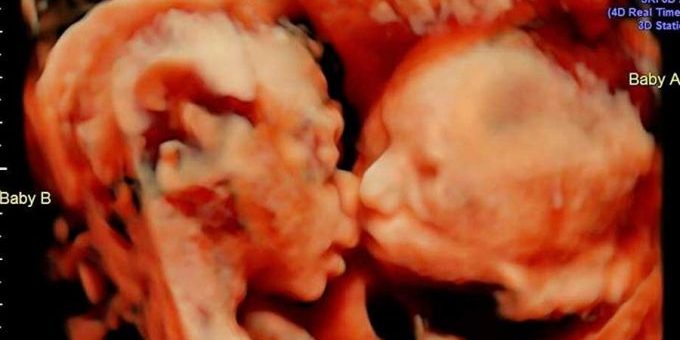

Uma mulher norte-americana com 25 semanas de gravidez descobriu algo curioso quando fez uma ultrassonografia: viu suas gêmeas dando um terno beijo.

No início de abril, Carissa Gill foi com seu noivo, Randy Good, ao centro de ultrassom Fetal Vision, em Levittown, no estado da Pensilvânia. Ambos ficaram surpresos quando viram no ultrassom que as suas primeiras filhas, Isabella e Callie, estavam frente a frente e parecia que uma delas estava dando um beijo na outra.

O médico que fez o ultrassom, John Hamburg, expressou ao jornal ‘The Huffington Post’ que a imagem é verdadeira e que “fez cerca de 15 mil dessas, mas nunca havia visto dois gêmeos frente a frente como se estivessem se beijando. Normalmente, a cabeça de uma está em cima e a do outro em baixo”.

Prevê-se que Isabella e Callie nasçam no final de junho. O casal indicou que imprimirão a imagem do ultrassom e colocarão no quarto das pequenas.